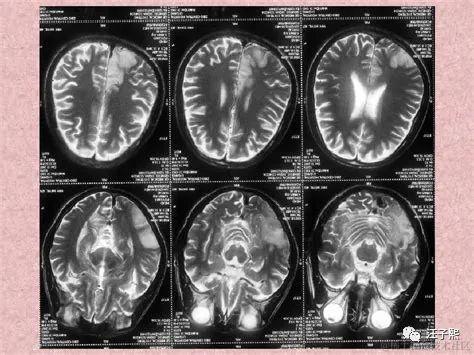

我见没有达到目的,换了一个角度继续问,“Z医生,从我前天拍的核磁共振检查报告来看,明天的手术,切除肿瘤难度大吗? ” 出乎我意料,这次Z医生没有给出诸如“有一定的难度”这样的答复,而是给我讲述了一些常识。放射科出具的核磁共振检查报告结果,就是病人拿给外科大夫看的那一张张黑乎乎的塑料片子,到底是怎么生成的呢?这要从我们是如何进行核磁共振检查说起。

参加核磁共振检查的人,会平躺在一个装置上(有点像电影《普罗米修斯》里女主伊丽莎白-肖博士进行剖腹手术,取出自己体内异形使用的手术仓),这套装置会产生一个特殊的磁场,并发出无线电射频脉冲激发人体内的氢原子核,引起氢原子核共振,并吸收能量。在停止射频脉冲后,氢原子核按特定频率发出射电信号,并将吸收的能量释放出来,被检查装置的接受器收录,通过计算机处理生成图像,这就是做核磁共振成像的一个完整流程。

Z医生告诉我,“你三天前的核磁共振片子结果,仅仅是你当时颅内的一个二维投影,我们可以用来作为参考进行手术难度评估,但它不是评估手术难度的决定性依据。一切都只能到了手术中,进入颅内看到实时情况,才能准确下结论。 ” 我心想,嗯嗯,我明白,核磁共振其实就是颅内实时状态,在某个时间点上给它做的一个镜像(snapshot), 这个镜像把颅内状况从3维降成了2维,根据该镜像无法逆向还原制作镜像那个时间点内的颅内状况。